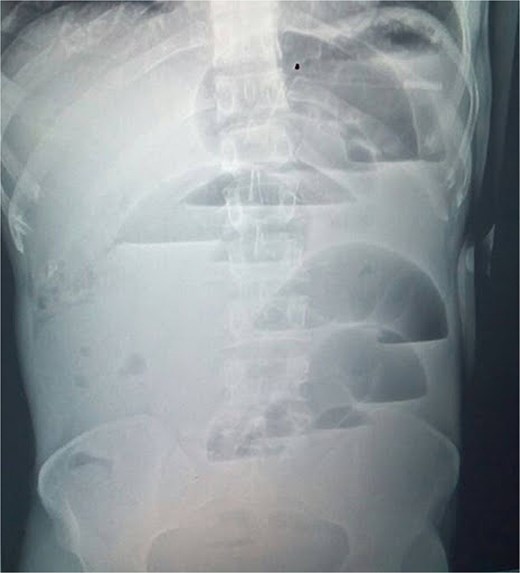

The laboratory findings included hemoglobin at 13.2 g/dl, a white blood cell (WBC) count of 9.4 × 109/l (78% neutrophils), platelets at 256 × 109/l; sodium at 138 mmol/l, potassium at 3.1 mmol/l, chloride at 102 mmol/l, bicarbonate at 24 mmol/l, creatinine at 0.8 mg/dl, and lactate at 1.2 mmol/l; urine pregnancy test was negative. Erect abdominal radiograph (24 hours from symptom onset) showed multiple central air–fluid levels and dilated small bowel loops (Fig. 1). Without prior surgery, adhesive obstruction was unlikely. The differential diagnoses included internal hernia, strangulated external hernia, ileo-sigmoid knotting, and rarer causes such as appendicular ileo-sigmoid knotting (AIK).

Erect abdominal radiograph showing multiple air–fluid levels and dilated bowel loops.